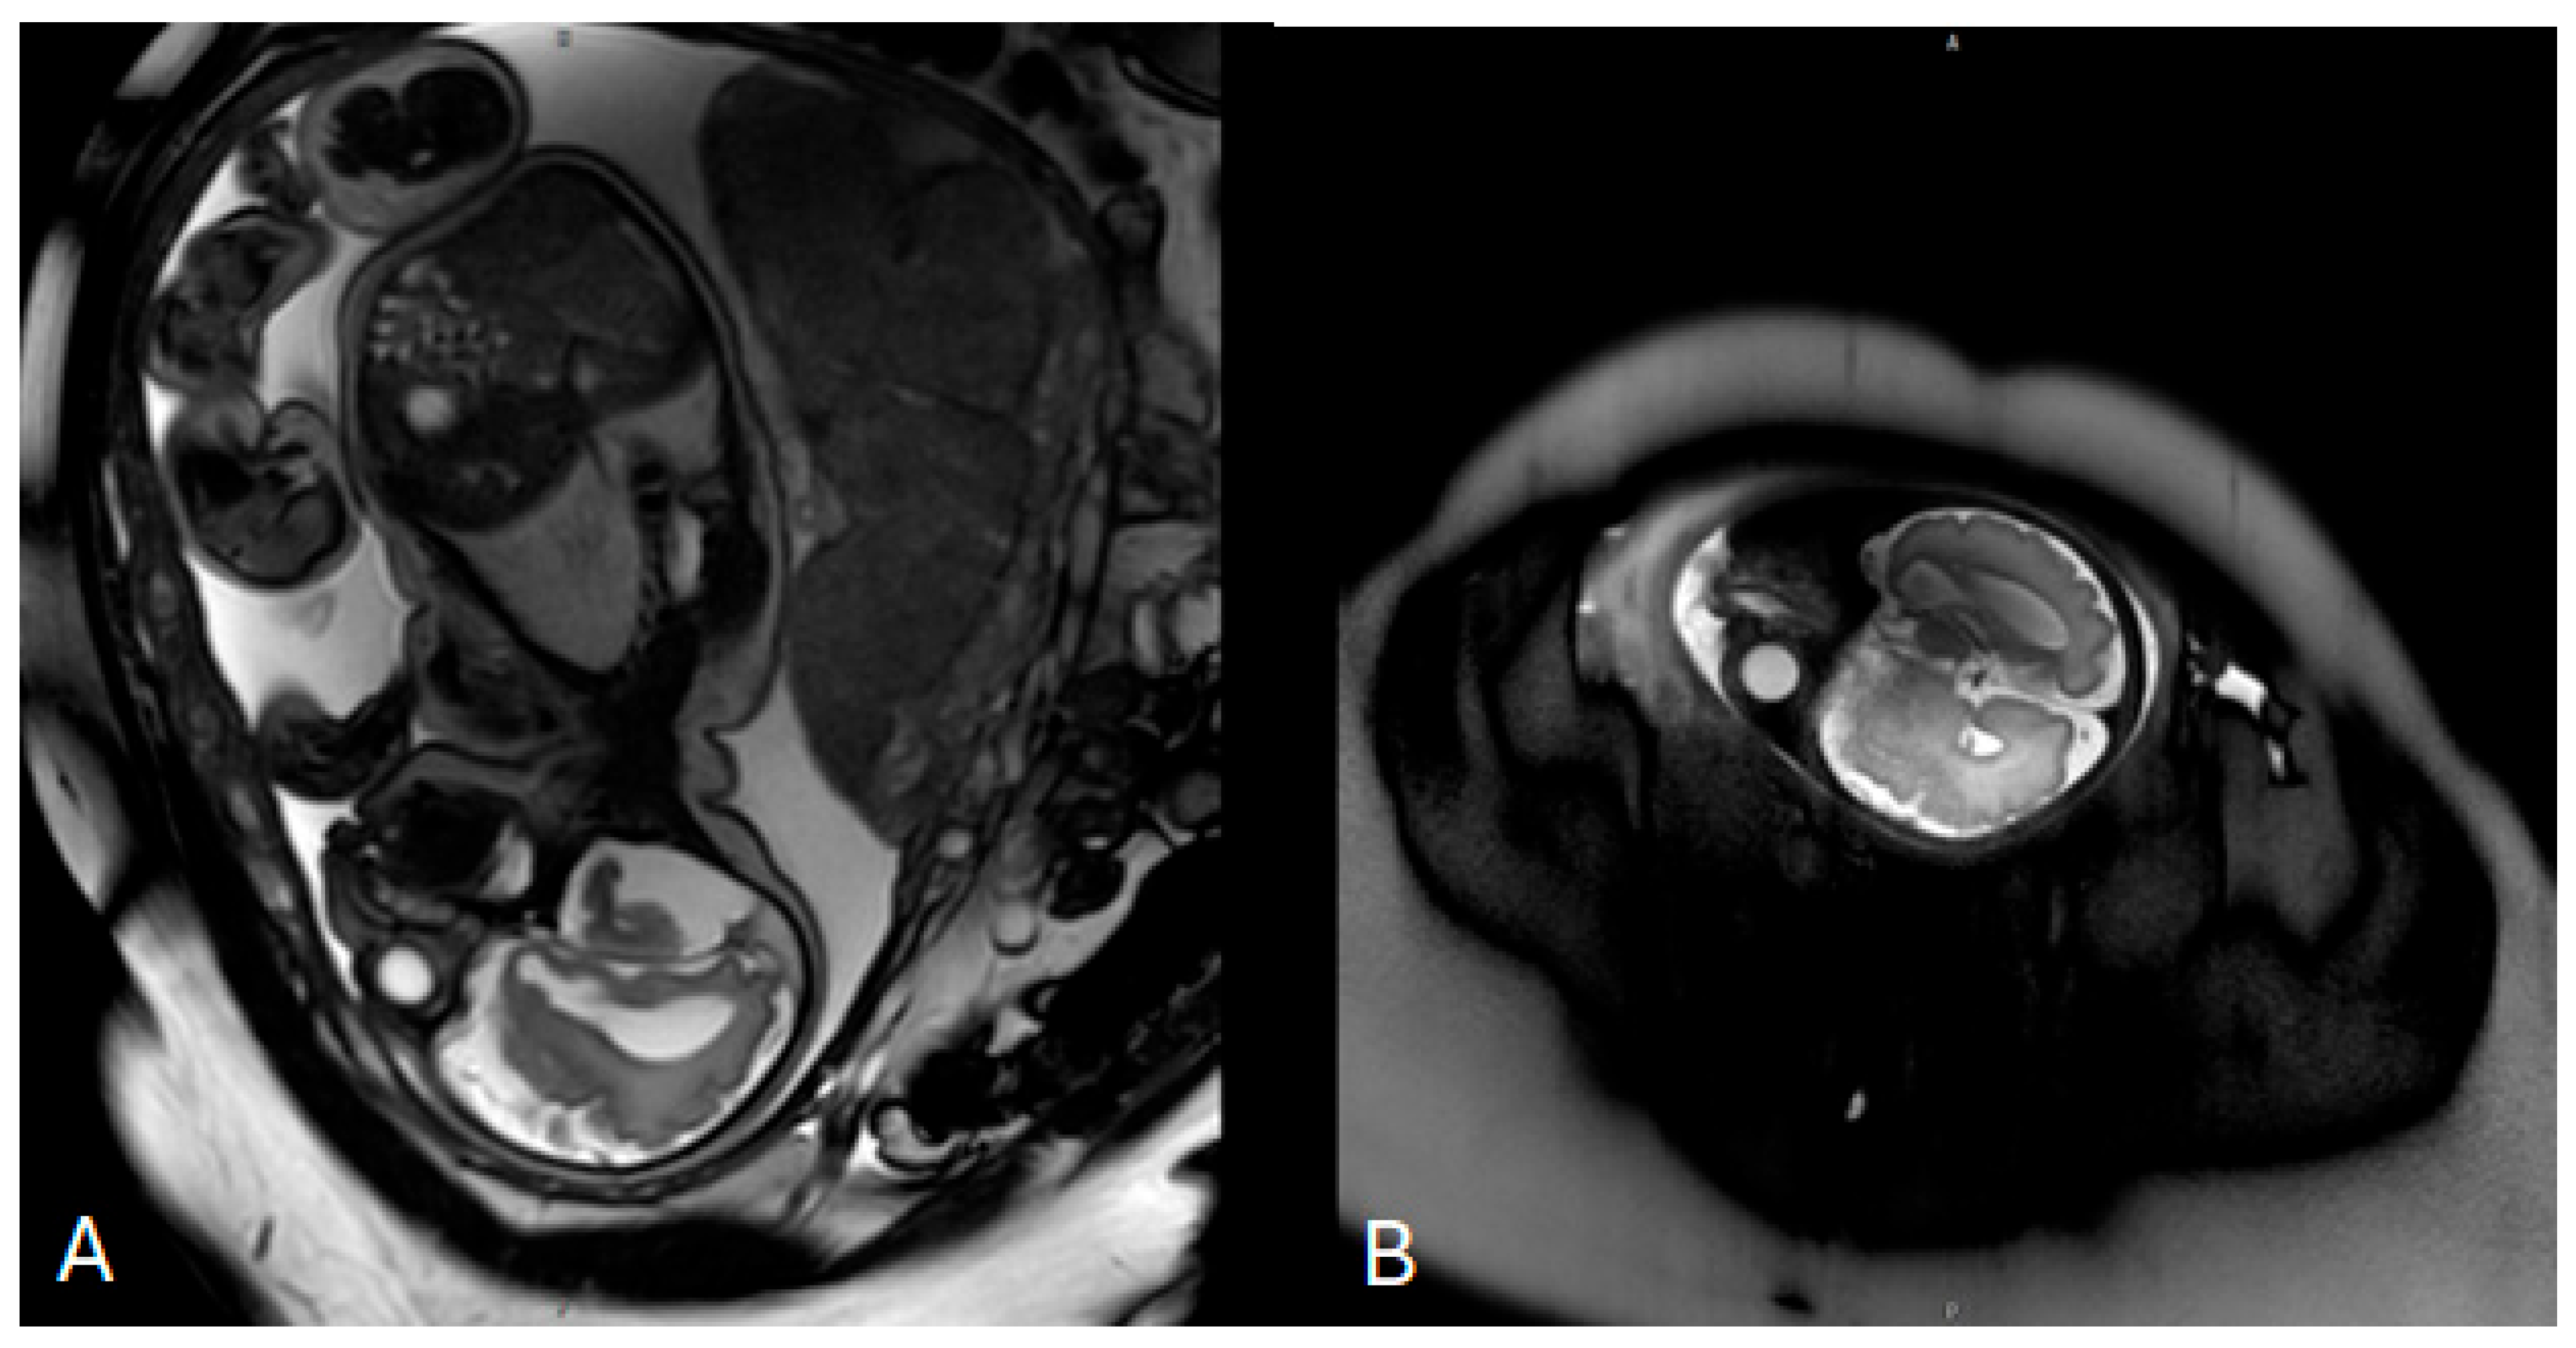

Invasive prenatal genetic testing was performed via amniocentesis. Conventional cytogenetic analysis revealed a normal female karyotype (46,XX). Multiplex ligation-dependent probe amplification (MLPA) for microdeletion and microduplication screening yielded negative results. This was followed by genome-wide chromosome sequencing (ChromoSeq, BGI VISTA™), which identified four copy number variants, all classified as variants of uncertain significance. No pathogenic chromosomal aneuploidies or clinically relevant microdeletions or microduplications were detected. Fetal magnetic resonance imaging (MRI) performed at 33 weeks of gestation demonstrated mild ventriculomegaly without evidence of neural tube defects (Figure 1). No further genomic testing was pursued during pregnancy, and prenatal consultation with a clinical geneticist was not documented.

Figure 1.

Prenatal fetal magnetic resonance imaging (MRI) performed at 33 weeks of gestation. (A) Axial T2-weighted image of the fetal brain demonstrating mild bilateral ventriculomegaly with visualization of the lateral ventricles. (B) Sagittal T2-weighted image confirming ventricular enlargement without additional major structural brain malformations at the time of examination.